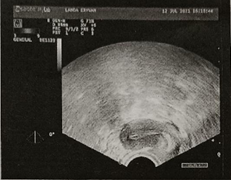

患者为27岁女性,最近一次就诊时间为2022-06-11。 主诉:正常性生活、未避孕、未孕5年。 既往史和家族史:既往体健。患有桥本甲状腺炎5年。否认高血压、糖尿病及各种慢性病史。 初潮年龄:13岁。 月经史:周期6-7个月,经期2-3天,量少。 生育史: 足月产次数(T):0; 早产次数(P):0; 流产次数(A):0; 存活子女数(L):0。 绝经相关症状:轻度。 Kupperman评分:7。 骨密度:-1。 体格检查:血压、身体质量指数(BMI)正常。 实验室检查: 2020年9月,患者AMH<0.06 ng/ml,TGAb为1764.03 IU/mL和TPOAb为1089.91 IU/mL。 2021年6月,患者甲状腺功能七项异常,促甲状腺激素(TSH)、TGAb和TPOAb均偏高,总体结果如下: 三碘甲状腺原氨酸(T3):1.275 ng/ml; 甲状腺素(T4):7.73 μg/dL; 游离三碘甲状腺原氨酸(FT3):5.17 pmol/L; 游离甲状腺素(FT4):14.38 pmol/L; TSH:14.187 μIU/mL; TGAb:865.52 IU/mL; TPOAb:981.53 IU/mL。 其他检查结果提示患者肝酶略高,血糖、血脂不高,染色体正常。 妇科检查: 2021年7月,患者彩超检查结果如下: 子宫前位,大小约34x30x24mm,形态规整,肌层回声均匀,内膜厚约6.8mm,回声均匀,宫颈厚约21mm,子宫体积小; 双侧卵巢显示不清; 子宫直肠凹陷可见范围约24x8mm的液性暗区; 体颈交界处子宫动脉血流:右阻力指数(RI)0.8,搏动指数(PI)2.08;左侧RI0.76,PI2.16,S/D4.25,盆底积液。 提示阴道宫颈正常,子宫偏小,附件未触及异常。